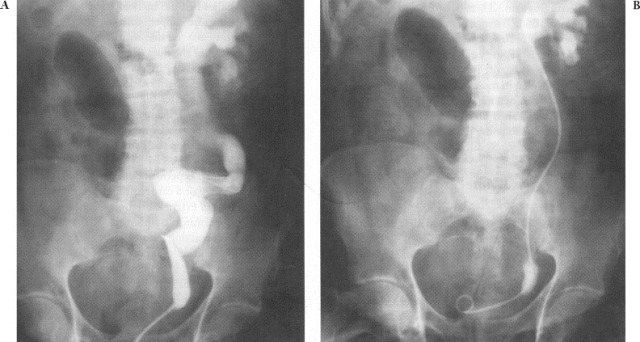

Ureteropyelography retrograde, atau disebut juga sebagai pyelografi retrograde, merupakan kombinasi pemeriksaan sistoskopi dengan pemeriksaan sinar-X menggunakan zat kontras untuk melihat kandung kemih, ureter, dan pelvis renalis. Sistoskop dimasukkan melalui uretra ke dalam kandung kemih untuk melihat struktur bagian dalam. Dengan alat ini, sebuah kateter bisa dipasang untuk memasukkan zat kontras ke dalam ureter, sehingga bisa tampak pada pemeriksaan sinar-X.

• Kateter bisa dipasang pada salah satu atau kedua ureter dan zat kontras akan dimasukkan melalui kateter

• Dilakukan foto sinar-X serial dengan interval waktu tertentu

• Kateter perlahan-lahan dilepaskan dan dilihat apakah terdapat retensi zat kontras